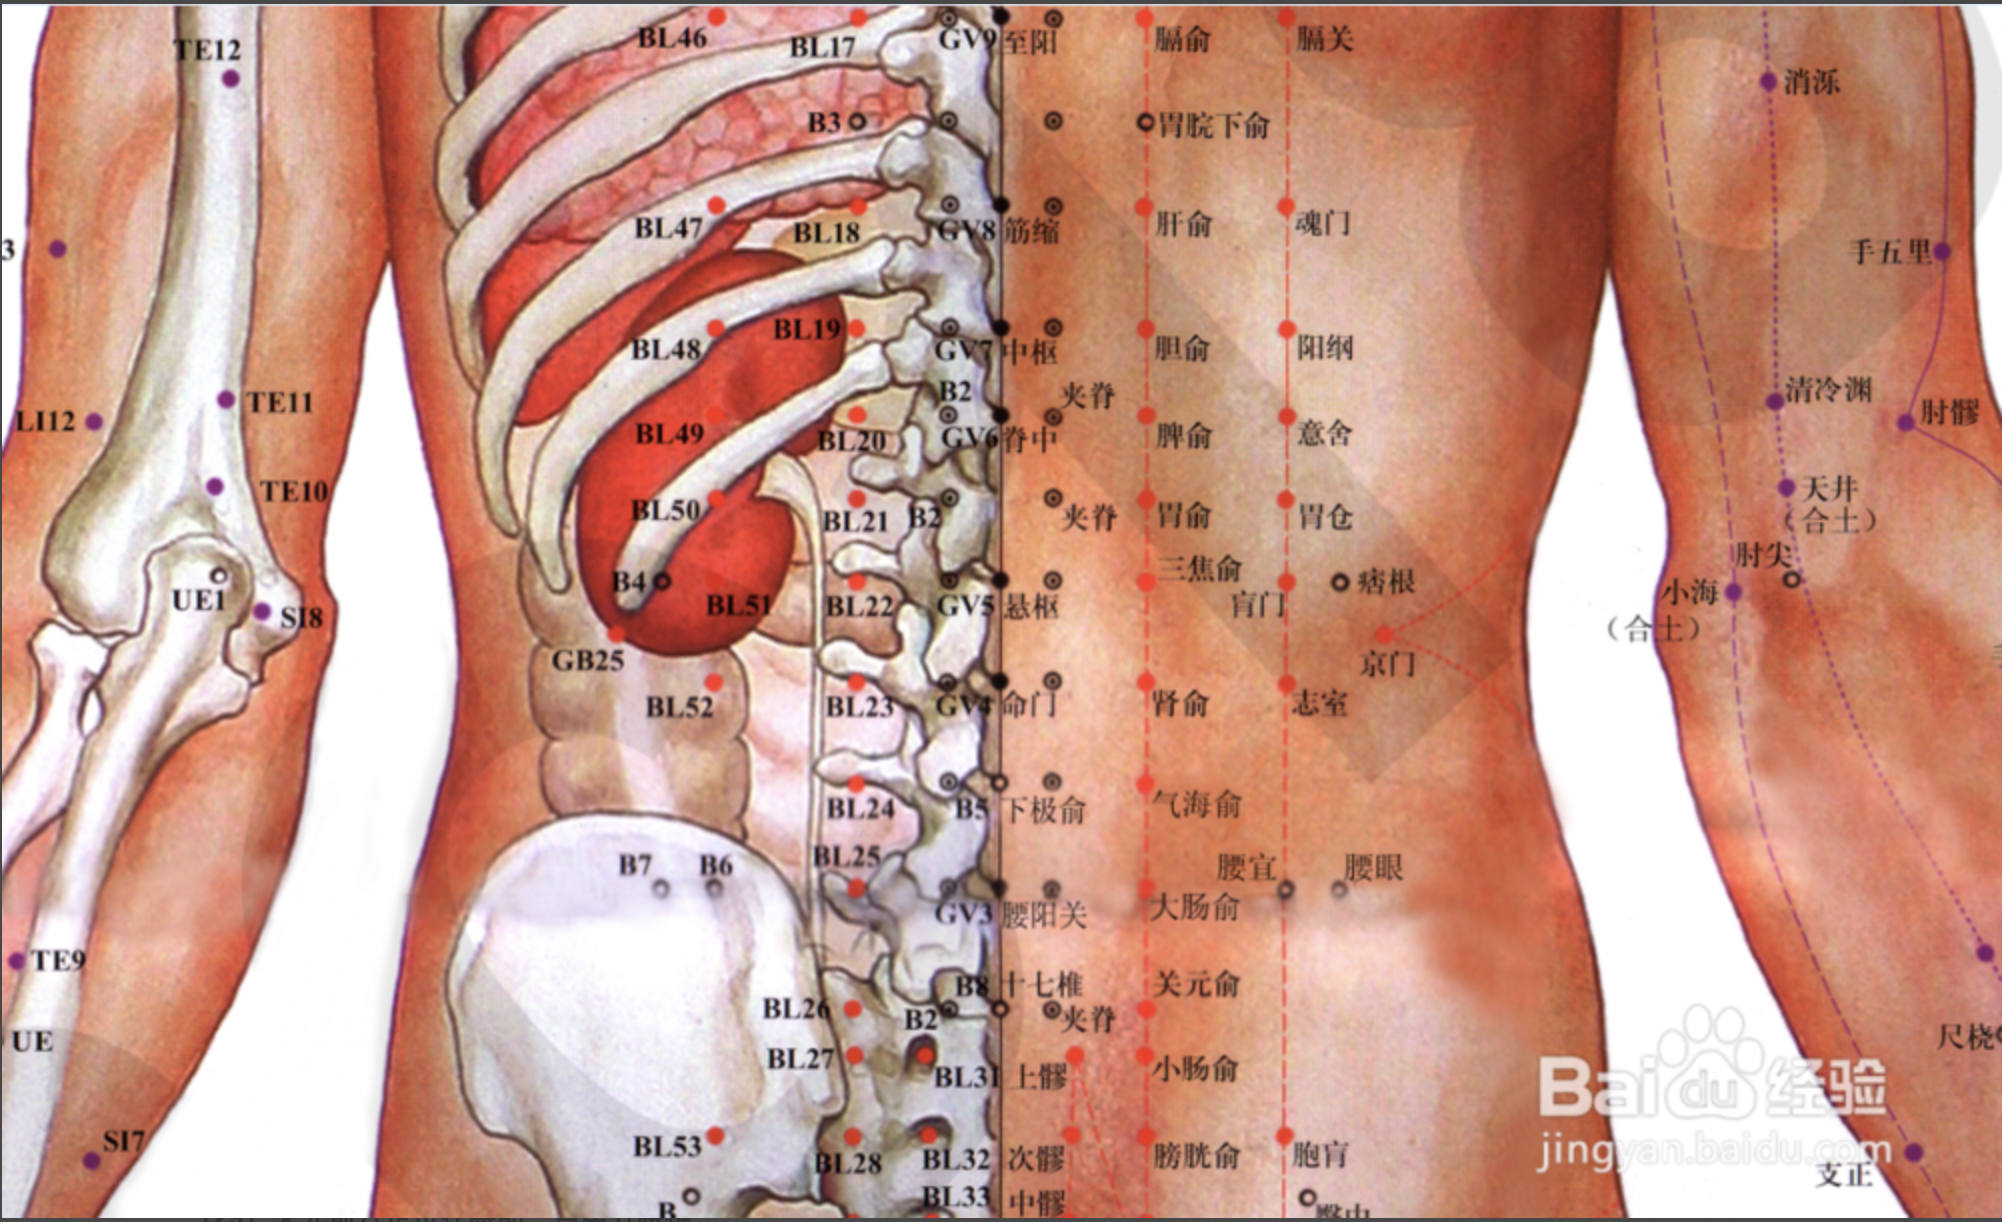

【(七)足太阳膀胱经(图 10-25-1)】

4、主要病候 小便不通,遗尿,癫狂,疟疾,目痛,见风流泪,鼻塞多涕,鼻衄,头痛,项、背、臀部及下肢循行部位痛麻等。

3、主治概要 主治头、项、目、背、腰、下肢部病证及神志病,背部第一侧线的背俞穴及第二侧线相平的腧穴,主治与其相关的脏腑病证和有关的组织器官病证。

肝俞

【定位】 在背部,当第 9 胸椎棘突下,旁开 1.5 寸。

【主治】 黄疸,胁痛,吐血,目赤,目眩,雀目,癫狂痫,脊背痛。

【配伍】 配支沟、阳陵泉治胁痛,配太冲治目眩。

【刺灸法】 斜刺 0.5 ~ 0.8 寸。

【附注】 肝的背俞穴。

胆俞

【定位】 在背部,当第 10 胸椎棘突下,旁开 1.5 寸。

【主治】 黄疸,口苦,胁痛,肺痨,潮热。

【配伍】 配阳陵泉、太冲治胆道疾病。

【刺灸法】 斜刺 0.5 ~ 0.8 寸。

【附注】 胆的背俞穴。

脾俞

【定位】 在背部,当第 11 胸椎棘突下,旁开 1.5 寸。

【主治】 腹胀,黄疸,呕吐,泄泻,痢疾,便血,水肿,背痛。

【配伍】 配足三里治腹胀、便秘。

【刺灸法】 斜刺 0.5 ~ 0.8 寸。

【附注】 脾的背俞穴。

胃俞

【定位】 在背部,当第 12 胸椎棘突下,旁开 1.5 寸。

【主治】 胸胁痛,胃脘痛,呕吐,腹胀,肠鸣。

【配伍】 配中脘、梁丘治胃痛。

【刺灸法】 斜刺 0.5 ~ 0。8 寸。

【附注】 胃的背俞穴。

肾俞

【定位】 在腰部,当第 2 腰椎棘突下,旁开 1.5 寸。

【主治】 遗尿,遗精,阳痿,月经不调,白带,水肿,耳鸣,耳聋,腰痛。

【配伍】 配太溪、三阴交治月经不调,配翳风,耳门治耳鸣、耳聋。

【刺灸法】 直刺 0.5 ~ 1 寸。

【附注】 (1)肾的背俞穴。(2)据实验观察:针刺对正常人水负荷后肾脏泌尿功能的影响,发现在大多数情况下,针刺肾俞或京门穴时可抑制肾脏的泌尿功能。

大肠俞

【定位】 在腰部,当第 4 腰椎棘突下,旁开 1.5 寸。

【主治】 腹胀,泄泻,便秘,腰痛。

【配伍】 配气海、足三里、支沟治便秘。

【刺灸法】 直刺 0.8 ~ 1.2 寸。

【附注】 大肠背俞穴。

上髎(liáo)

【定位】 在骶(dǐ)部,当髂(qià)后上棘与后正中线之间,适对第 1 骶后孔处。

【主治】 大小便不利,月经不调,带下,阴挺,遗精,阳痿,腰痛。

【配伍】 配三阴交、中极治小便不利。

【刺灸法】 直刺 1 ~ 1.5 寸。

次髎

【定位】 在骶(dǐ)部,当髂(qià)后上棘与后正中线之间,适对第 2 骶后孔处。

【主治】 疝气,月经不调,痛经,带下,小便不利,遗精,腰痛,下肢痿痹。

【配伍】 配三阴交、中极、肾俞治遗尿,配血海治痛经。

【刺灸法】 直刺 1 ~ 1.5 寸。

中髎

【定位】 在骶部,当次髎下内方,适对第 3 骶后孔处。

【主治】 便秘,泄泻,小便不利,月经不调,带下,腰痛。

【配伍】 配足三里治便秘。

【刺灸法】 直刺 1 ~ 1.5 寸。

下髎

【定位】 在骶部,当中髎下内方,适对第 4 骶后孔处。

【主治】 腹痛,便秘,小便不利,带下,腰痛。

【配伍】 配气海治腹痛。

【刺灸法】 直刺 1 ~ 1.5 寸。

腰阳关

【定位】 在腰部,当后正中线上,第 4 腰椎棘突下凹陷中(图 10-30-2)。

【主治】 腰骶疼痛,下肢痿痹,月经不调,赤白带下,遗精,阳痿,便血。

【配伍】 补腰阳关、肾俞、次髎,泻委中治腰脊痛、四肢厥冷、小便频数;配腰夹脊、秩边、承山、飞扬治坐骨神经痛、腰腿痛;配膀胱俞、三阴交治遗尿、尿频。

【刺灸法】 直刺 0.5 ~ 1 寸;可灸。

命门

【定位】 在腰部,当后正中线上,第 2 腰椎棘突下凹陷中(图 10-31-2)。

【主治】 虚损腰痛,脊强反折,遗尿,尿频,泄泻,遗精,白浊,阳痿,早泄,赤白带下,胎屡坠,五劳七伤,头晕耳鸣,癫痫,惊恐,手足逆冷。

【配伍】 配肾俞、太溪治,遗精、早泄、腰脊酸楚、足膝无力、遗尿、癃闭、水肿、头昏耳鸣等肾阳亏虚之争;配百会、筋缩、腰阳关治破伤风抽搐,灸命门、隔盐灸神阙治中风脱症;配关元、肾俞、神阙(艾灸)治五更泄,补命门、肾俞、三阴交治肾虚腰痛,泻命门、阿是穴、委中、腰夹脊穴治腰扭伤痛和肥大性脊柱炎,配十七椎、三阴交(艾灸)治痛经(寒湿凝滞型),配大肠俞、膀胱俞、阿是穴(灸)治寒湿痹腰痛。

【刺灸法】 直刺 0.5 ~ 1 寸;可灸。